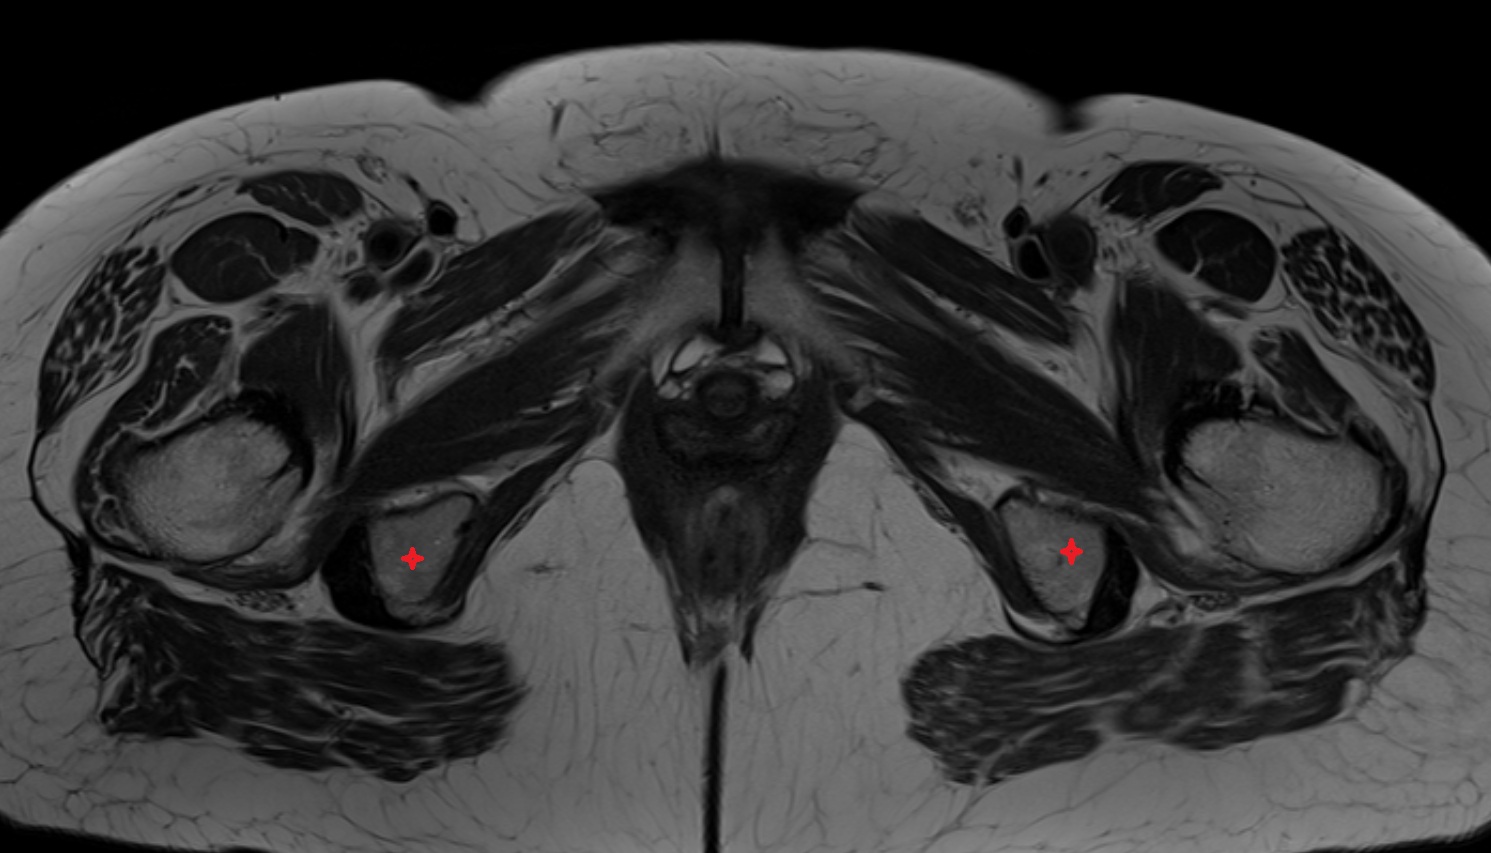

- Testis

- Tunica albuginea (penis)

- Tunica albuginea of testis

- Epididymis

- Head of epididymis

- Tail of epididymis

- Body of epididymis